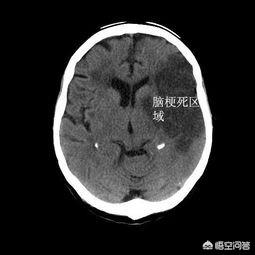

但就其治疗效果来看,因脑细胞是不可再生的,一旦发生脑梗死以后,目前的治疗手段是不可能回复如初,所以可以称之为“医学难题”!

组织学上“治愈”,现代医学尚不能实现;

但功能上的“治愈”,在某种程度上是可以实现的,如一些患者脑梗后缺损症状完全恢复,日常生活基本不受影响!